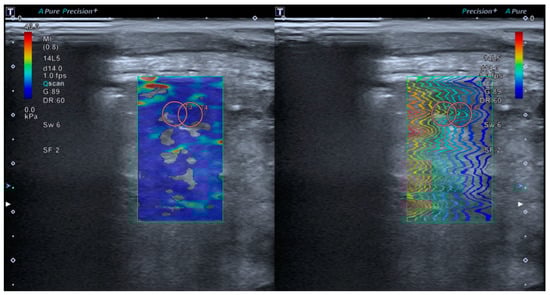

2.4.2. Lung Shear Wave Elastography Acquisition

Tissue elastance will be measured using lung SWE through an intercostal window, minimizing the manual pressure applied by the transducer. The SWE ‘Multi’ mode (Real-Time Shear Wave acquisition) will be activated, triggering a dual screen (TwinView), where the elastance map will be displayed on the left and the propagation map on the right (Figure 3). A colored box will be placed 1 cm from the capsule on the elastance map (with an elastance scale set at 40 kPa). Subsequently, a circular Region of Interest (ROI) of 10 mm (size 5 on our device) will be selected, with a measurement depth limited to a maximum of 5 cm. Measurements will preferably be taken in areas with homogeneous color on the elastance map and with shear wave propagation as parallel as possible. Of all the measurements taken, the two with the lowest standard deviation and an interquartile range (IQR) < 0.3 will be selected, and their mean value will be used for inclusion in the final statistical analysis.

Figure 3. The TwinView feature of the Aplio A500 device (Canon™) allows for the visualization of the elastance map (left) and the propagation map (right).